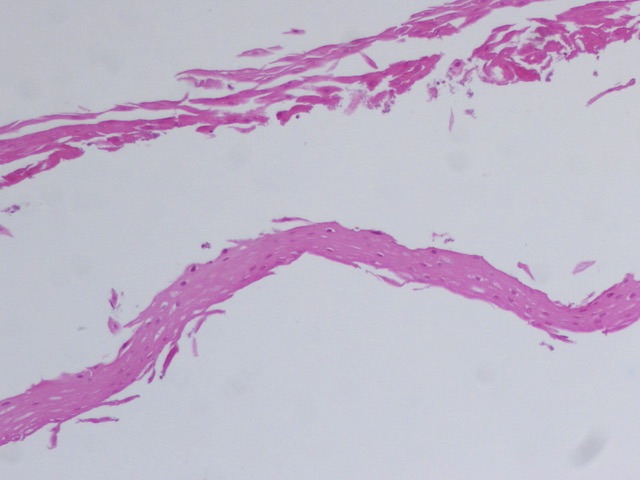

#GIPath #Diagnosethis #Pathresidents 1/2 Look what crossed my my microscope ? The key is in the bitonal hue of this esophagus with sharply demarcated layers ,strong pink superficial ,intraepithelial cleft ,partially detached ,other fragments with just strips of superficial